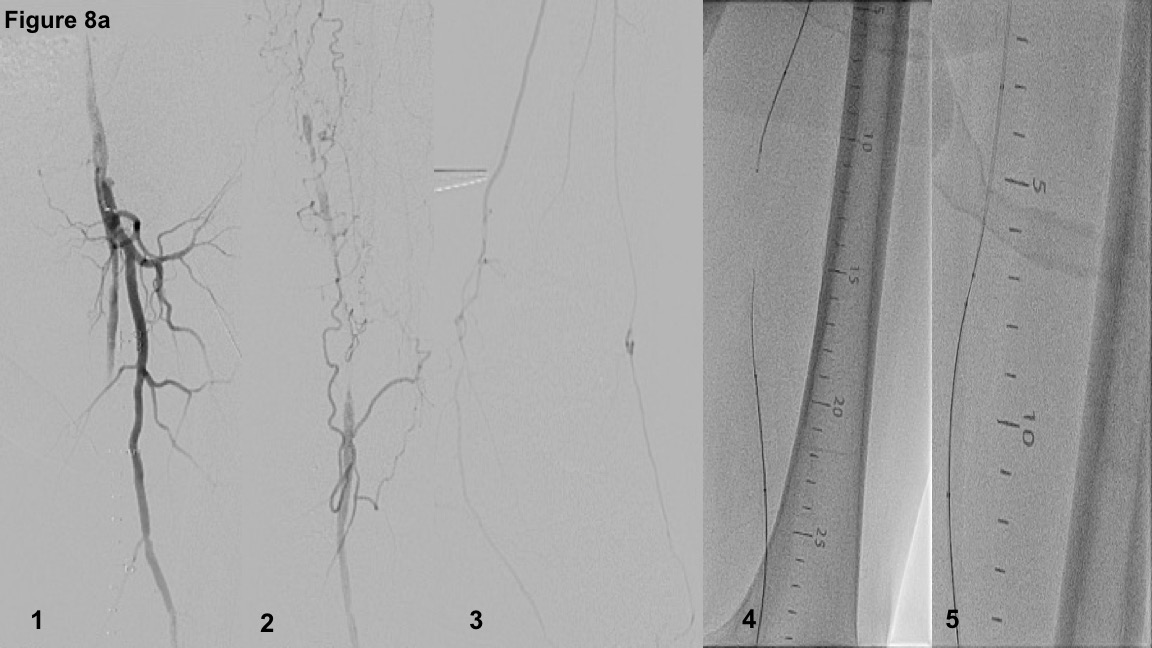

Figure 8 illustrates a case of a long (330 mm) FP-CTO in a claudicant with a previous failed crossing attempt. CTO cap assessment revealed CTOP type II (Figure 8A-Panels 1 and 2). Figure 8A-Panel 3 depicts two-vessel pedal run-off. The lesion is classified as type IIIC and successfully crossed using a hybrid approach. An unsuccessful antegrade attempt using guidewire escalation with Regalia (Asahi Intecc) followed by Astato 20 (Asahi Intecc) was initially employed. Following passage of the antegrade guidewire in a distal SFA subintimal dissection plane similar to the prior crossing attempt, retrograde crossing via a posterior tibial approach was performed (Regalia guidewire in a .035˝support catheter; Figure 8A-Panel 4). The base of operations was established in the mid SFA by retrieving the antegrade .035˝ support catheter to accept the retrograde guidewire (the rendezvous technique; Figure 8A-Panel 5) followed by wire externalization and drug-coated balloon treatment. The selection of the mid SFA base of operation allows placement of a short mid SFA stent at the re-entry zone without stenting the distal SFA and popliteal artery.